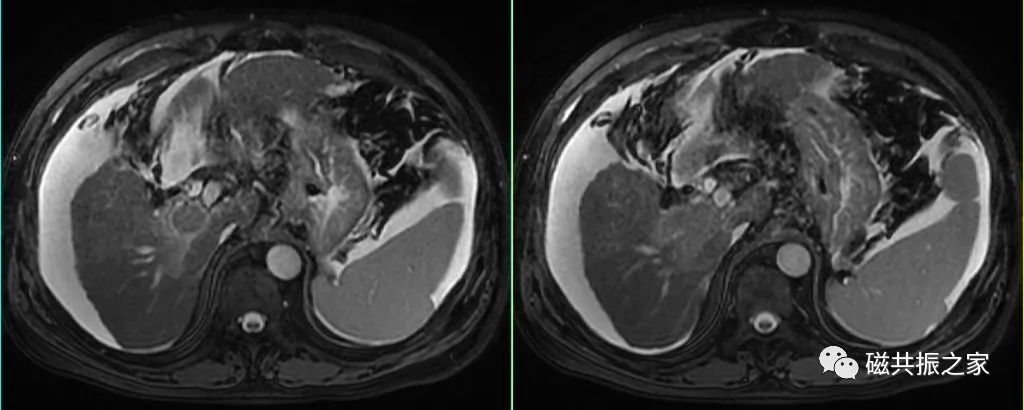

横轴面:横轴面T2WI脂肪抑制序列

在矢状位和冠状位上定位。扫描范围上至肝顶,下至十二指肠,合理调整扫描范围,需包括整个病变范围。

呼吸触发的横轴位T2WI脂肪抑制序列是上腹部扫描的“黄金序列”,做好该序列是关键,可结合如螺旋桨等技术来改善呼吸、血管搏动及胆囊蠕动的运动伪影。

对于呼吸不均,采用呼吸触发获得的图像质量较差时,可采用屏气的超长回波链-T2WI序列或单次激发T2WI序列或稳态自由进动序列替代扫描,但应注意替代序列对其病变的敏感性和特异性。

替代序列可采用快速的FSE或GRE序列,但应注意其对病变的敏感性和特异性。